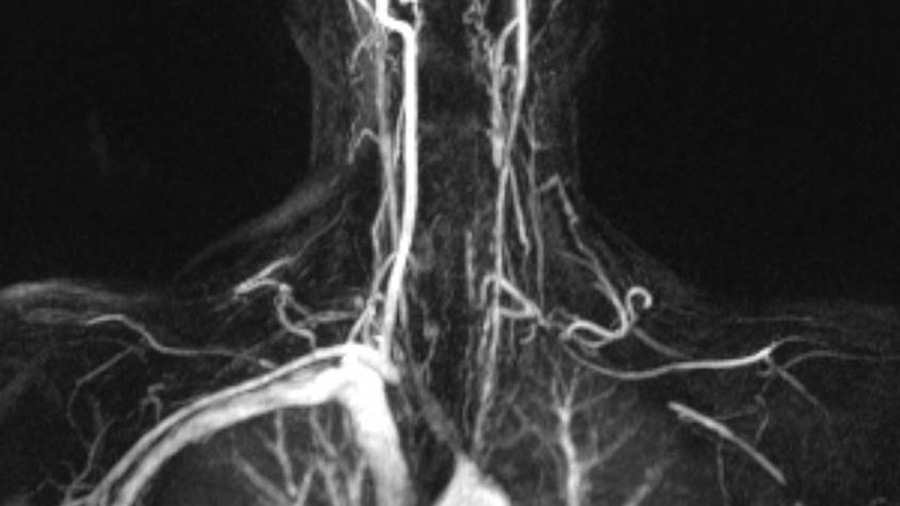

Vaskulitis verstehen

Mehr über die verschiedenen Formen, Symptome und Behandlungsmöglichkeiten von Vaskulitiden.